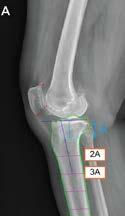

딥러닝 모델의 경골 후방 경사각 측정

메커니즘 (출처 서울대병원)

(서울=연합뉴스) 김잔디 기자 = 무

릎 관절의 안정성 등에 관여하는 정 강이뼈(경골)가 뒤쪽으로 얼마나 기

울었는지를 빠르고 정확하게 측정

할 수 있는 인공지능(AI) 모델이 국

내 연구진의 주도로 개발됐다.

서울대병원 정형외과 노두현 교수

연구팀은 2009년부터 2019년까지

촬영된 무릎 관절 측면 엑스레이 영

상 1만여건을 바탕으로 '경골 후방 경사각'을 측정할 수 있는 딥러닝 모

델을 개발했다고 26일 밝혔다.

경골 후방 경사각은 종아리 안쪽에

있는 경골을 옆에서 볼 때 관절이 얼

마나 뒤로 기울어져 있는지를 나타 내는 각도다. 무릎 관절의 안정성과 무릎 수술 후 인공관절 수명에

이 용해 경골의 기울기를 계산하는 AI 모델을 개발했다.

AI 모델의 측정 시간은 평균 2.5초 로, 전문의가 직접 측정하는 데 걸리 는 평균 26.1초보다 빨랐다.

AI 모델의 측정값은 전문의가 내놓 은 결과와 91% 일치했다.

연구 결과는 국제학술지 '스포츠 의학 정형외과 저널'(Orthopaedic Journal of Sports Medicine)에 게 재됐다.